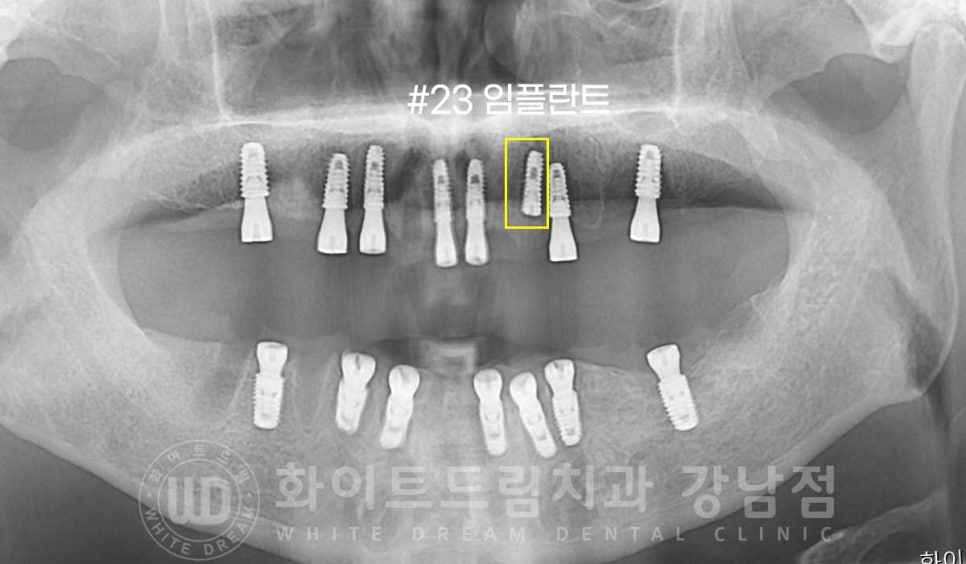

환자분은 골 소실이 심했던 부위, 23번 임플란트 부위는

뼈이식을 동반한 임플란트 치료를

동반하여 수술을 진행했고,

이 23번 임플란트는 보다 안정적이게 골 유착이 될 수 있도록

잇몸뼈 안에 매복을 해둔 상태로 수술을 완료하게 되었습니다.

내원 거리가 조금 머신 김포에서 내원을 하시는 분이셔서

최소한의 내원 횟수로 빠르게 치료를 받기를 원하셔서

총 2회의 수술로 나누어(상악 전체 식립, 하악 전체 식립) 전악 임플란트를 식립하기로

치료 계획을 세우게 되었습니다.